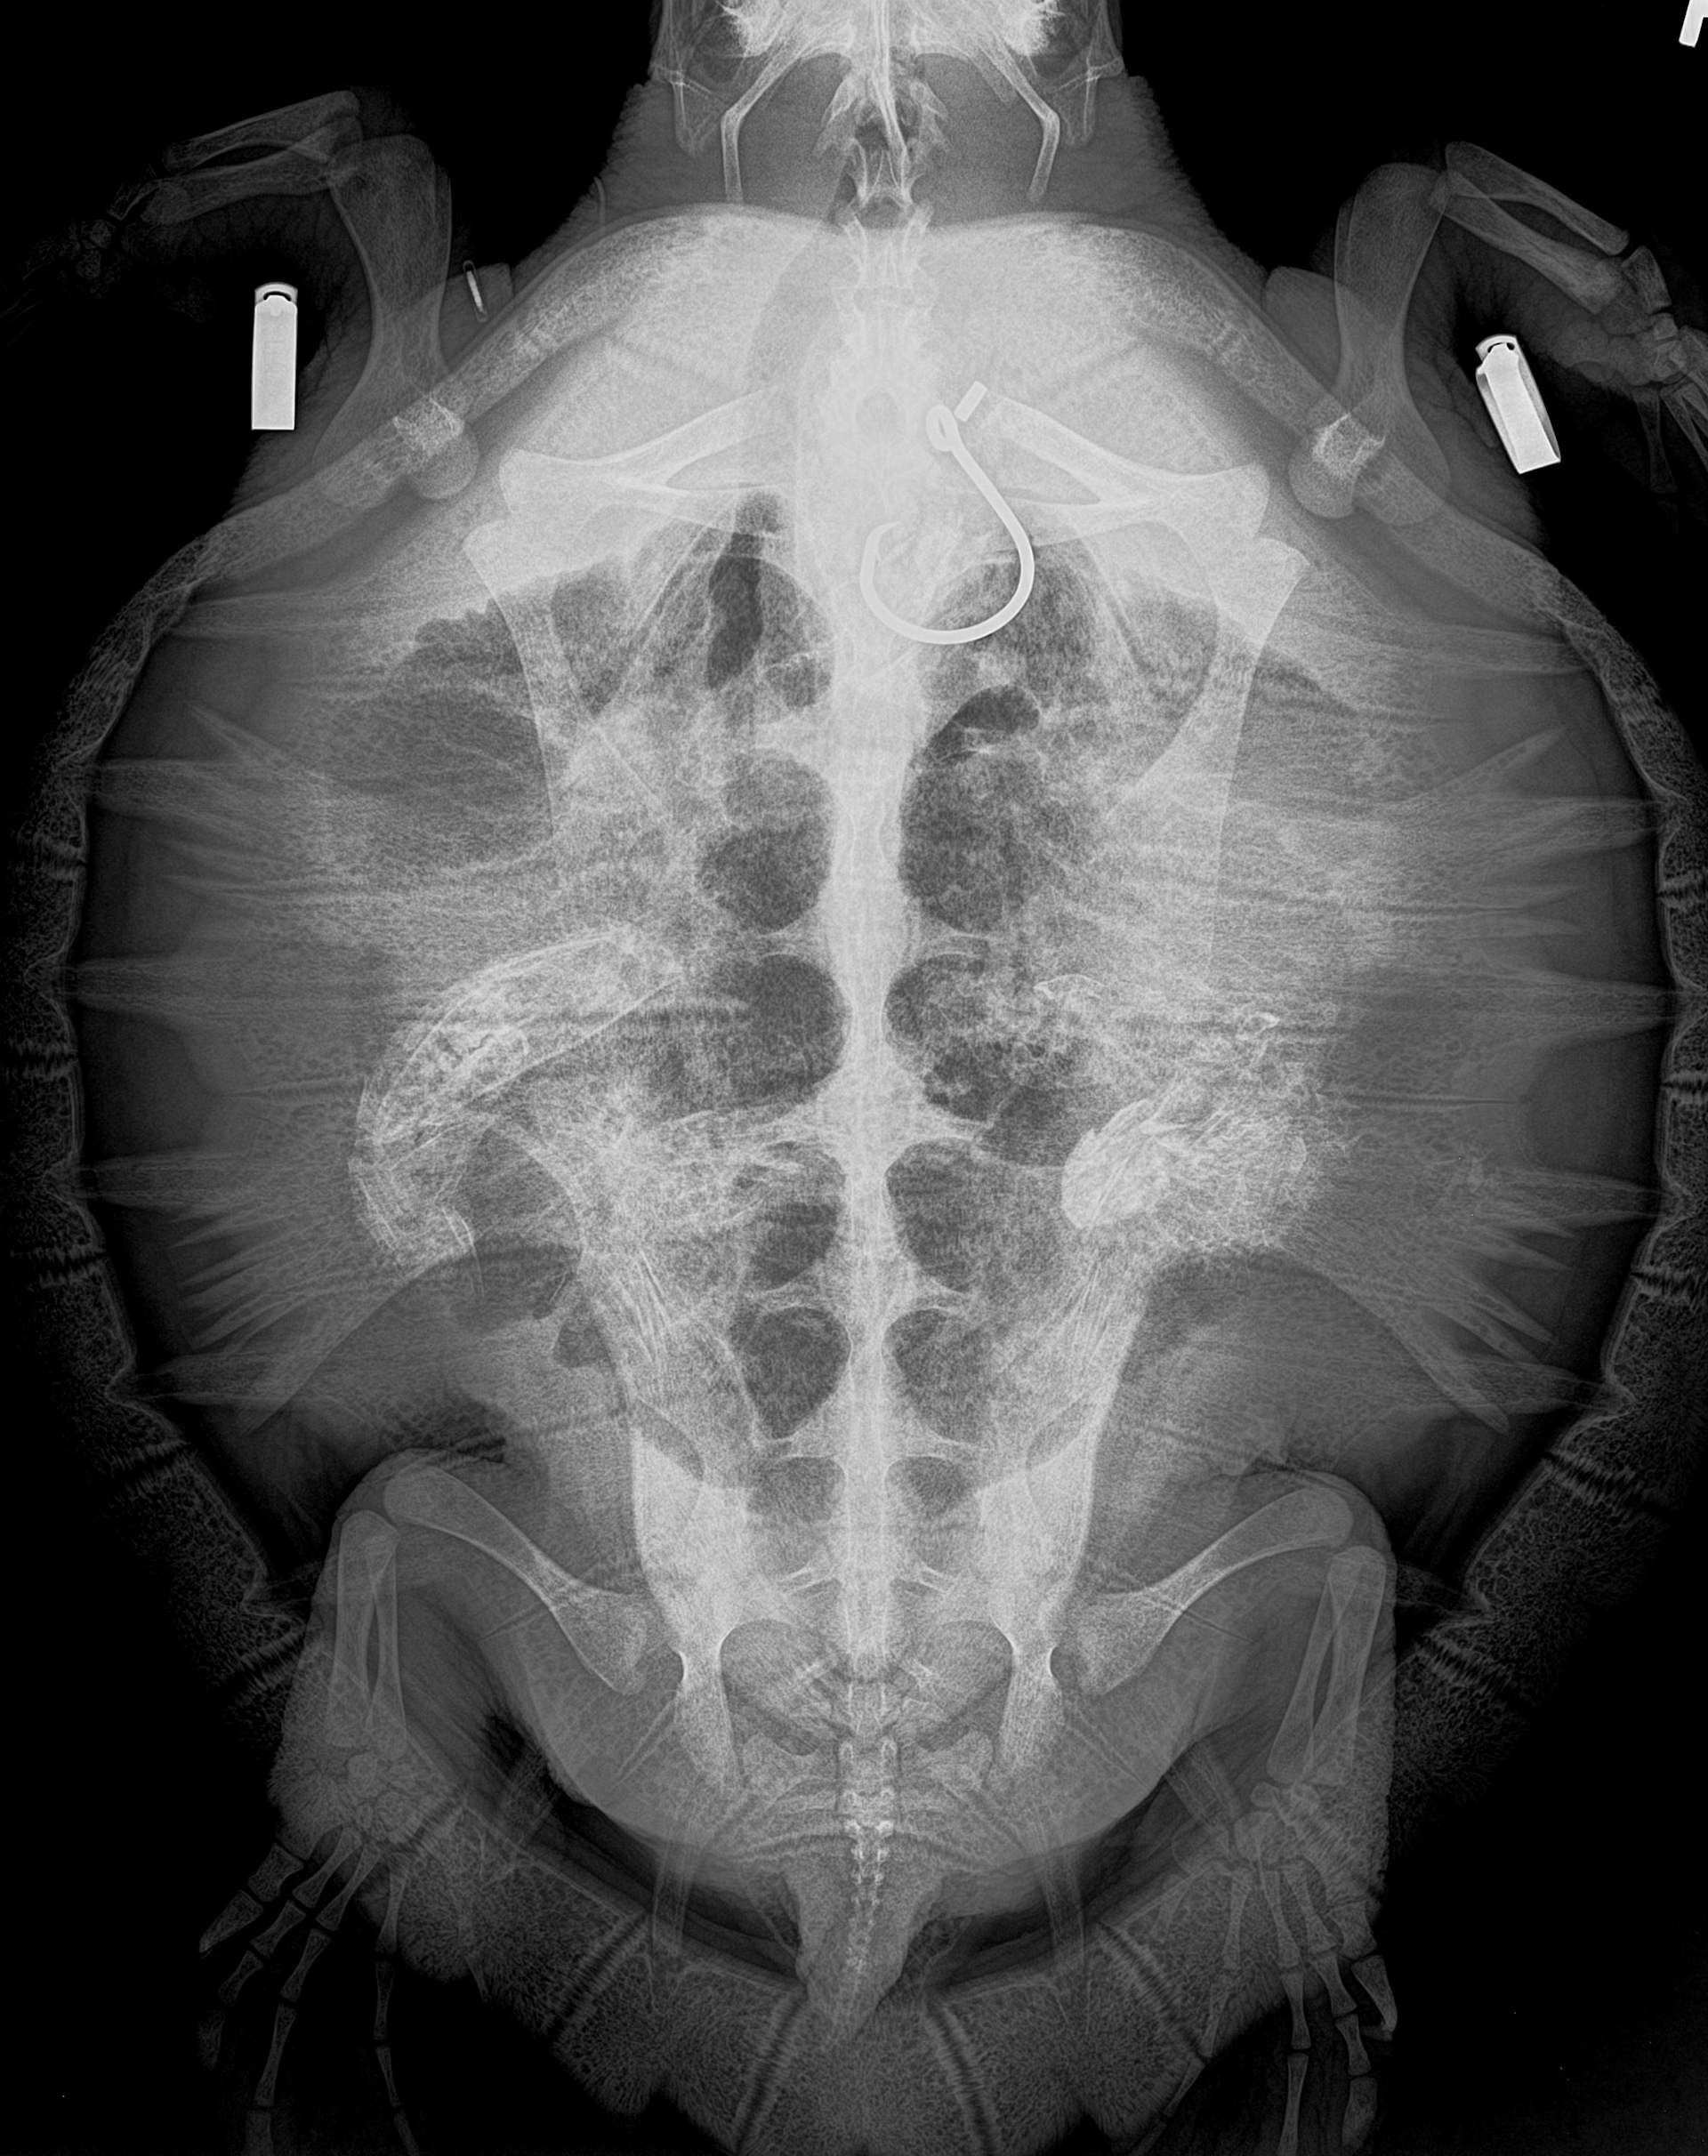

That summer afternoon, the sea turtle stranding team transported Toni to the veterinary hospital nearby at IMMS. Once at the hospital, Debra and the veterinary team took an X–ray and found that the hook was lodged deep in the turtle’s stomach. Getting it out would not be easy. Debra then called John to come to Gulfport to try to remove the hook with an endoscope.

We passed an endoscope – a long, thin tube with a camera and a light on the end – into the turtle’s esophagus and stomach. The esophagus connects the mouth to the stomach, and in most animals it is a smooth tube. But not in sea turtles. Sea turtles have hundreds of fingerlike projections called papillae that stick out in the esophagus to trap shrimp, crabs and other food in the stomach. Using the endoscope, we could see that the point of the hook was deeply embedded in the stomach, but the other half, which contained the eye of the fishing hook, was hidden behind some papillae. We needed to be careful to avoid tearing the stomach.

Once we got a good view of the hook, the team passed a small lasso through the scope. We needed to slide the lasso over the eye of the hook, then tighten it as close as possible to the point embedded in the turtle’s stomach – a challenging task, since the hook was lodged flat against the stomach wall and hidden by the papillae. But after four hours, our team was finally able to free the hook and pulled it out through the turtle’s mouth.